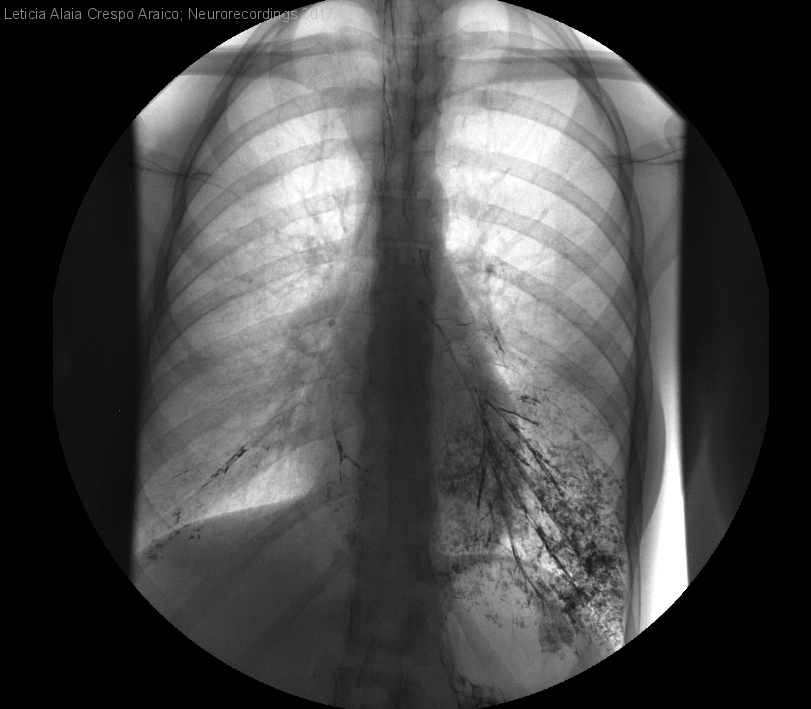

Mujer | 21 años

Diagnóstico final: Impresión basilar

Mujer de 21 años sin antecedentes personales ni familiares de interés que acude por disfagia progresiva para líquidos de 2 años de evolución y alteración de la marcha de cronología incierta."Tiene muy mal equilibrio" desde hace años. La paciente...